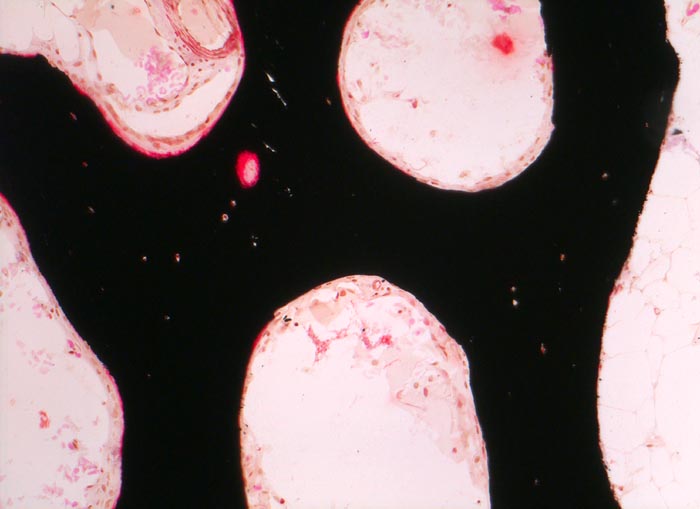

Morphologische Merkmale (Goldner Färbung):

• Verbreiterte unmineralisierte Osteoidsäume (rot).

• Reduzierte Menge von mineralisiertem spongiösem und kortikalem Knochen (grün).

• Schmale, rarefizierte und nur geringgradig vernetzte Knochenbälkchen bei Osteoporose.